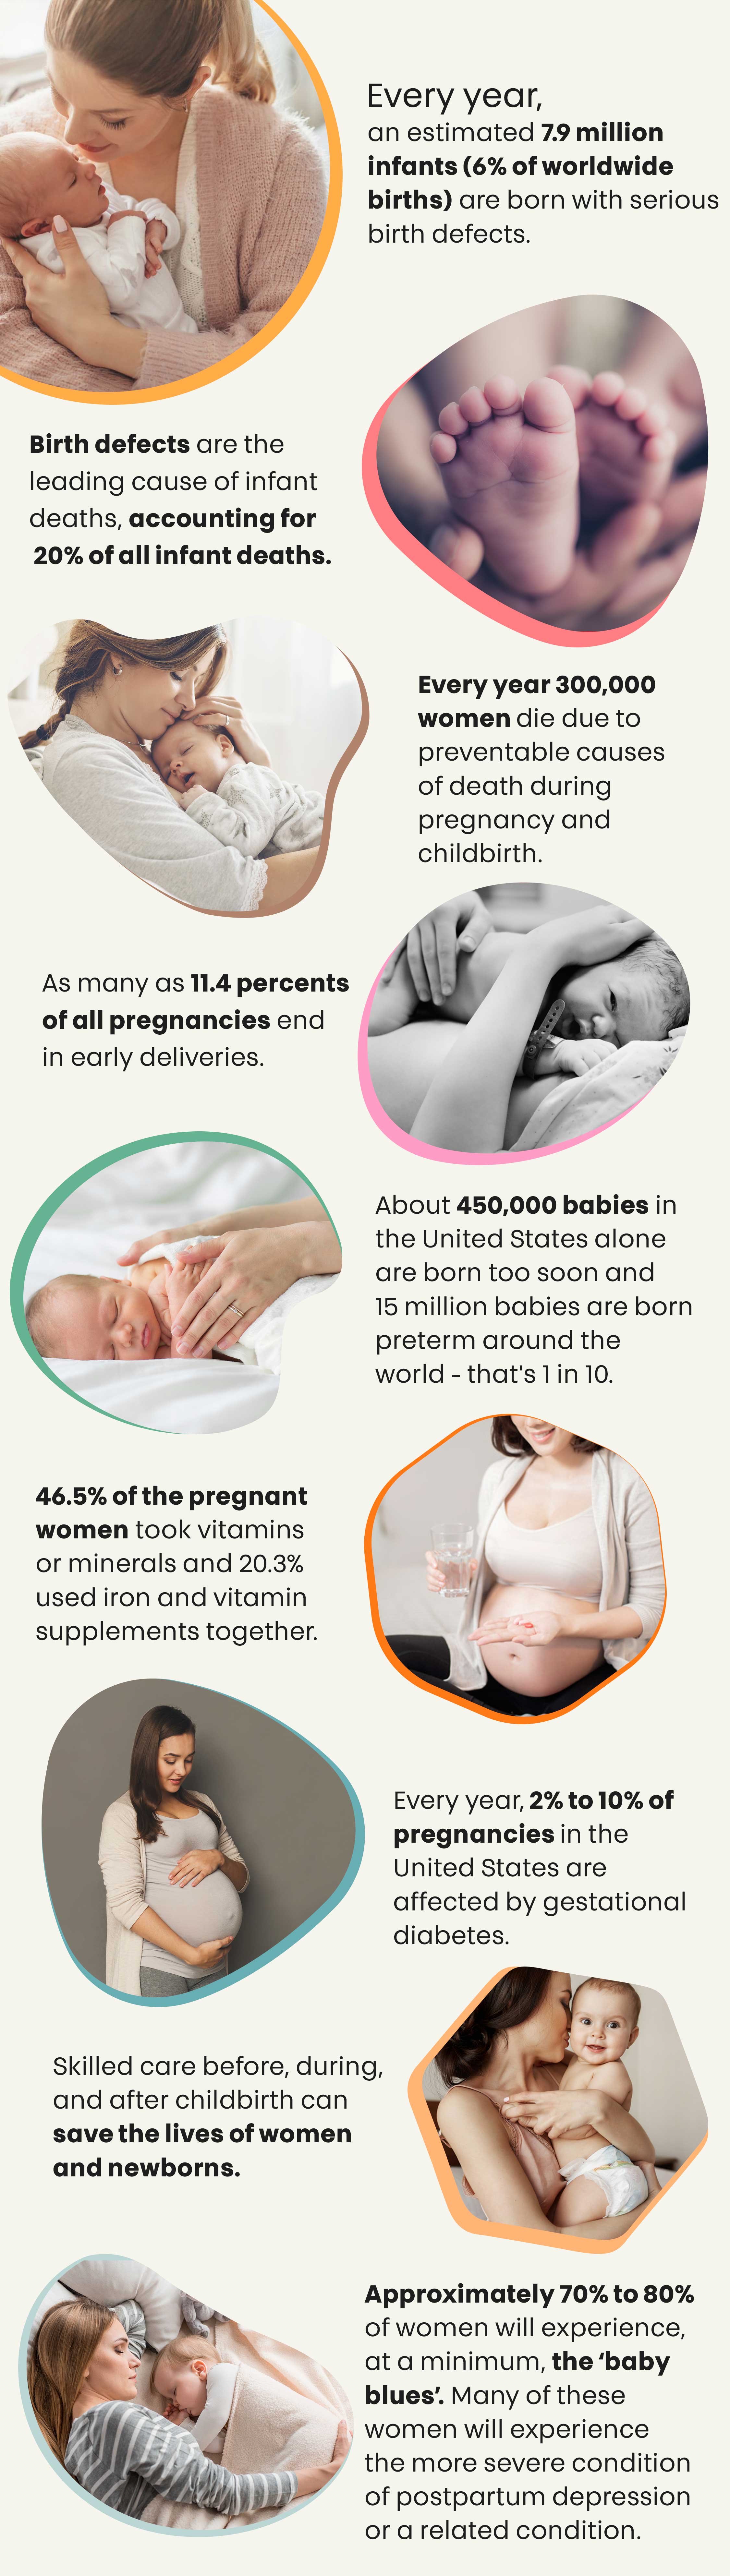

Are You Expecting And Worried About Your Baby’s Nutritional Needs?

Find Out Everything You Need To Know About Pregnancy Diet And Nutrition By Grabbing Our Top-Notch, High-Quality Info Guide To Avoid Birth Complications, Child Defects And Have A Happy & Healthy Pregnancy!!!